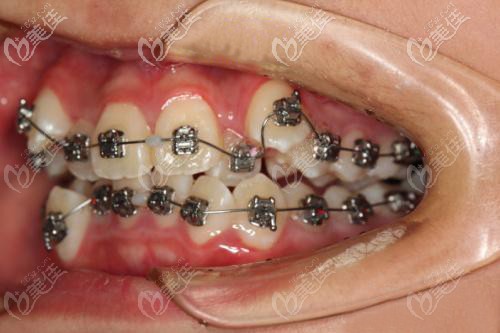

術(shù)后照片:

牙達(dá)人口腔漢陽店的正畸醫(yī)生給出的矯正方案:

方案一:常規(guī)思維設(shè)計(jì),采用拔掉4個(gè)4號牙的矯治方案,戴透明隱形牙套和金屬托槽都可以。

方案二:不拔牙,采用診斷性矯治設(shè)計(jì)方案,使用金屬自鎖托槽矯治器。

選擇不拔牙戴鋼絲自鎖牙套的原因:

1、是因?yàn)樾∶妹煤ε掳窝溃?/p>

2、擔(dān)心戴傳統(tǒng)的鋼牙套太過于磨嘴、不適,戴可摘戴的隱形牙套又嫌麻煩.....所以,就選擇了進(jìn)口的3M金屬自鎖托槽。

3、自鎖托槽上面少了結(jié)扎絲的捆綁,降低摩擦力,戴上相對會舒適一些,還能延長復(fù)診時(shí)間。

還有就是,我了解到未成年人的牙槽骨還在發(fā)育期,所以矯正的時(shí)間也要比成年人快一些,這位17歲的小妹妹就只用了14個(gè)月,成人的話少說也要2年左右。